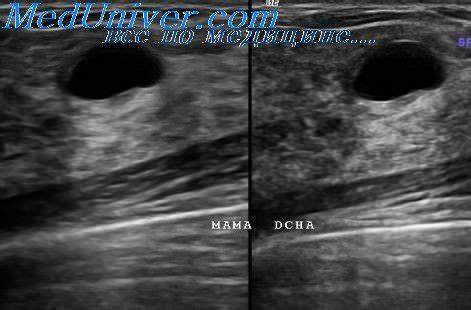

Картинка 6: Рак молочной железы на УЗИ: как выглядит? Покажет ли его УЗИ?